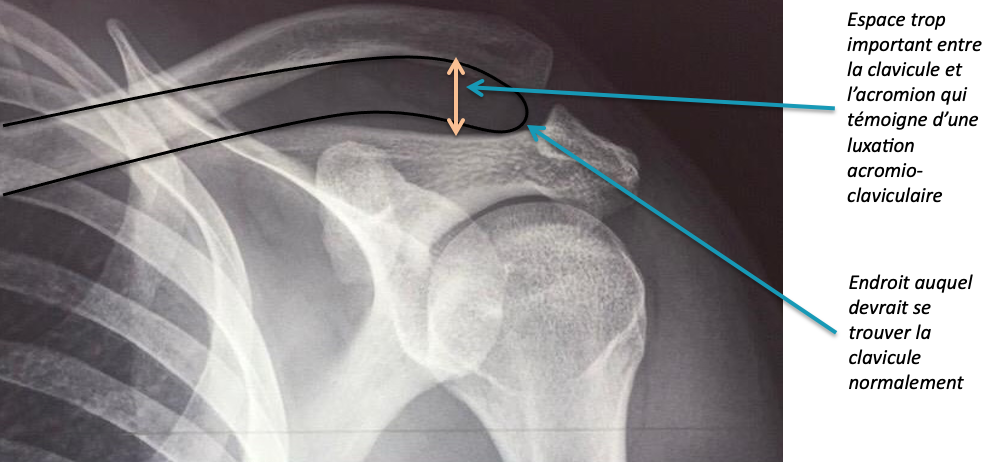

La mobilité de l’articulation acromio-claviculaire se fait parfois au détriment de sa stabilité. En effet, certains travaux ou activités sportives peuvent imposer de lourdes contraintes à l’épaule. Une luxation acromio-claviculaire est une séparation entre la clavicule et l’omoplate. Elle est généralement causée par une chute ou un coup sur l’épaule. La gravité d’une lésion de l’articulation acromio-claviculaire dépend des structures endommagées. Les lésions acromio-claviculaires sont classées en 6 catégories allant de la luxation légère peu grave à la séparation complète grave.

Les radiographies comparatives des deux épaules permettent de confirmer le diagnostic, d’évaluer la gravité de la blessure et d’éliminer une fracture de la clavicule.